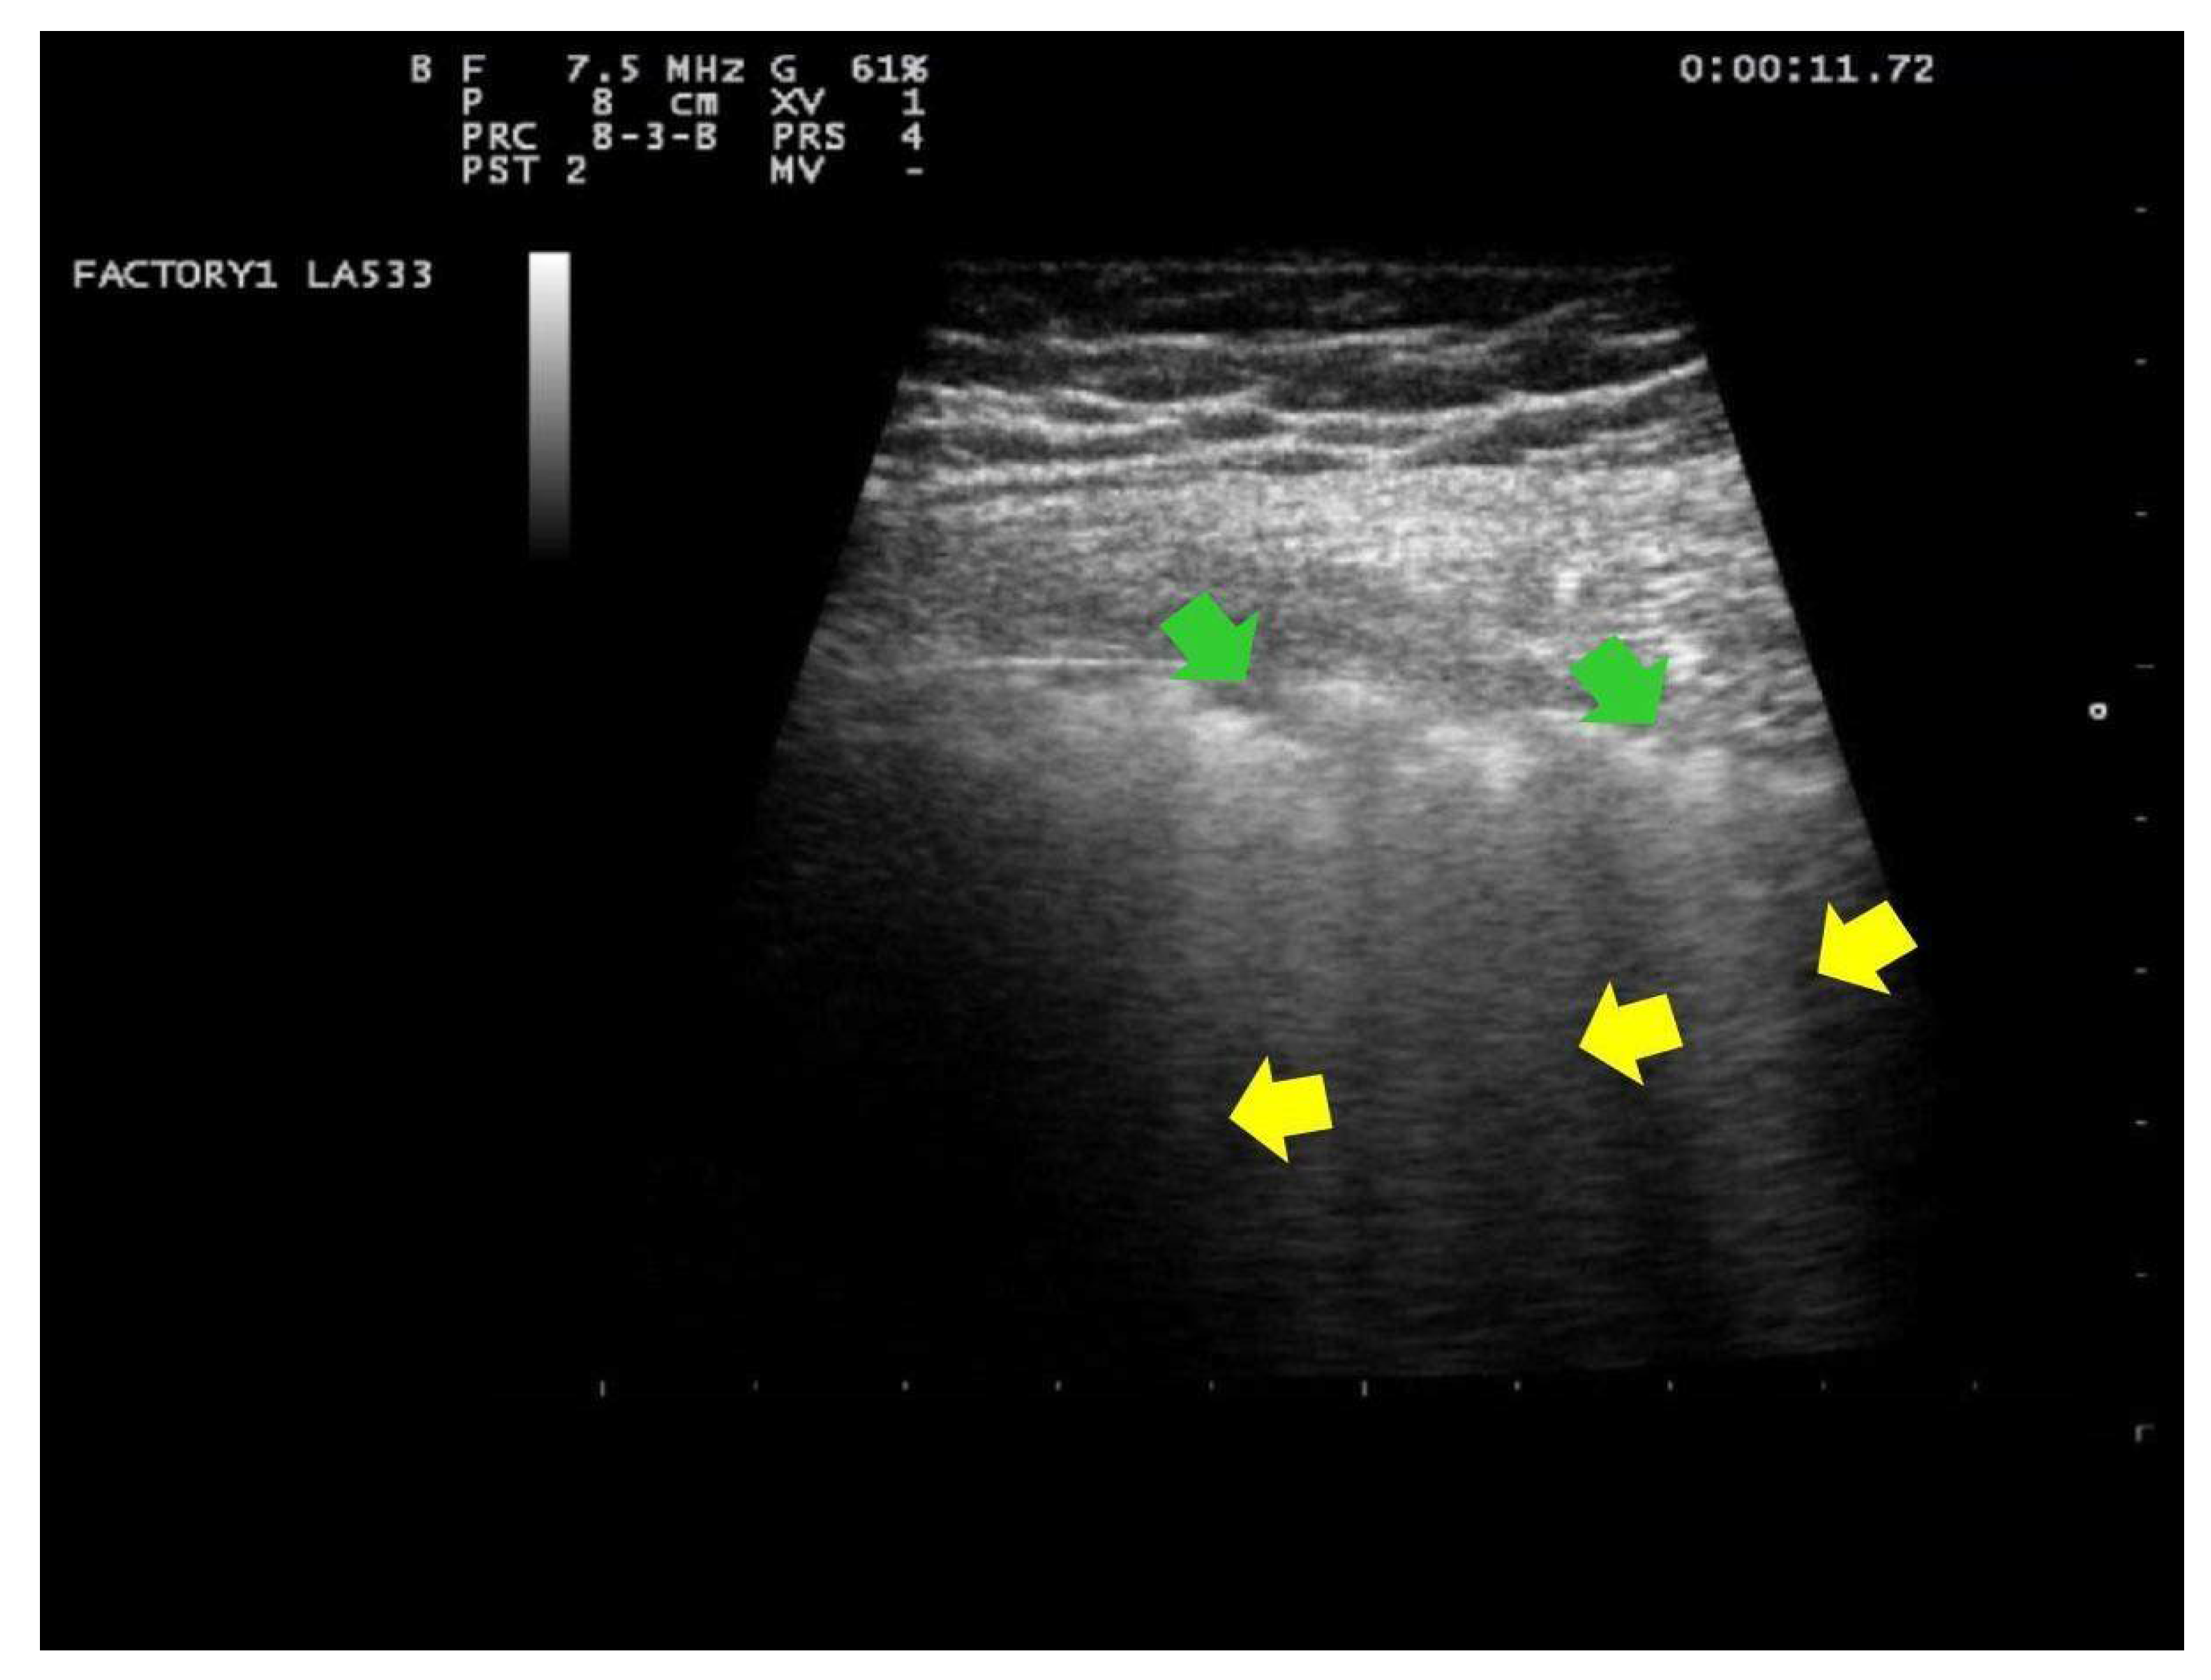

- Score 1:

- Score 1: at least three B-lines or confluent B-lines which occupy ≤ 50% of the screen without irregularities of pleural line. (Figure 2) Score 1p: B-lines with a clearly irregular pleural line.